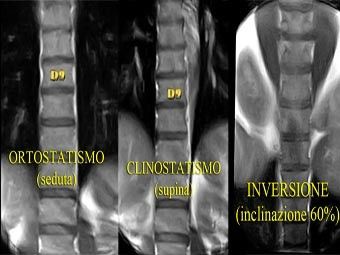

Durante la respirazione corrente, l’escursione del diaframma aumenta nella postura clinostatica (fig. 8, filmato 1)) rispetto all’ortostasi (fig. 9, filmato 2)), come già dimostrato in letteratura (Takazakura et al 2004); non sembra aumentare ulteriormente nella inversa (fig. 10, filmato 3) rispetto alla clinostatica. Il livello cranio-caudale dell’escursione cambia notevolmente tra orto e clino, portandosi dal livello del disco tra D11-D12 a livello del disco tra D9-D10. Tra il clino e l’inversione si cranializza ulteriormente ma non così evidente come tra clino e orto.

Dalla valutazione qualitativa effettuata viene confermato ciò che il letteratura (Takazakura et al 2004) è riportato a riguardo. Passando dalla postura ortostatica a quello in clinostatismo si assiste ad una evidente cranializzazione dell’escursione del diaframma durante la respirazione corrente. Si passa, infatti, dal livello del disco tra D11- D12 al disco tra D9-D10. Portando in inversione il soggetto si assiste ad una ulteriore cranializzazione, ma non così evidente come da orto a clino.